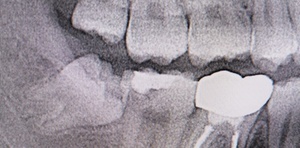

Before(下親知らずの抜歯前) 横に生えた状態で埋まっている親知らず 虫歯がある親知らず 抜歯前の骨の状態のレントゲン像

原因をより詳しく調べるためレントゲンを撮影したところ、右下の親知らずは骨の中に埋まった状態のまま真横に生えて隣接する歯を押しており、前方の歯が虫歯になっています。 そのため、右下の親知らずと隣の奥歯の間には、歯と歯ぐきの境目の溝である「歯周ポケット」が通常よりもかなり深くなっていました。

まず、親知らずと骨の中にある神経の位置、歯や周囲の骨の詳細な情報を確認するために、歯科用パノラマデジタル写真で口腔内を撮影します。撮影結果を踏まえ、抜歯方法や施術の難易度をしっかり確認しました。